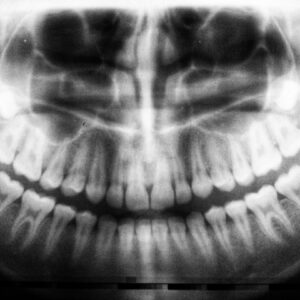

Photo Dental implant X-ray

What Are the Potential Costs Related to Emergency or Unplanned Visits to Address Dental Implant Complications?

When you consider the financial costs associated with dental care, it can be daunting. The expenses can quickly add up, especially if you require extensive treatments. From routine check-ups to…

Photo Dental X-ray

Are There Any Potential Costs Associated with the Removal of a Failed Dental Implant and Subsequent Replacement?

Dental implants have revolutionized the field of restorative dentistry, offering a durable and aesthetically pleasing solution for individuals who have lost teeth. These titanium posts are surgically embedded into the…

Are There Any Long-term Costs Associated with Potential Complications, Such As Peri-implantitis or Implant Failure?

When you consider dental implants, you likely envision a long-lasting solution to missing teeth. However, it’s crucial to understand that not all implants are immune to complications. Peri-implantitis is one…